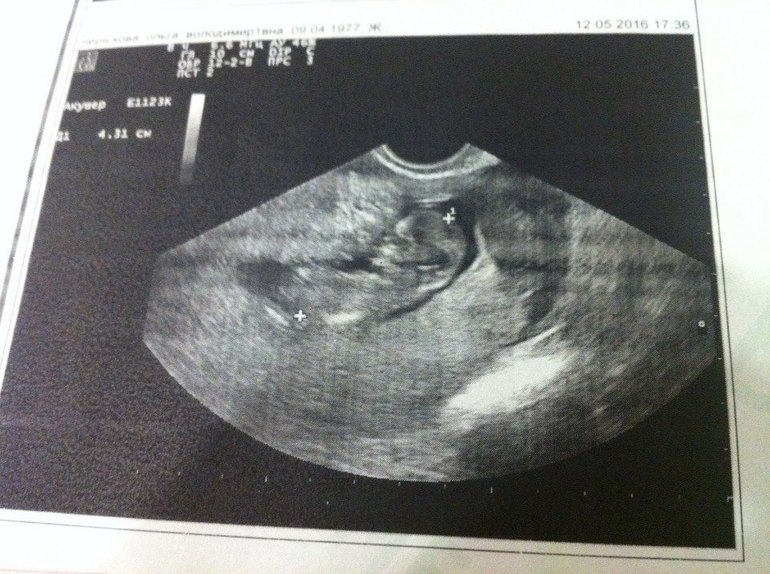

УЗИ, КТГ, доплерСегодня, перед дорогой домой, сходила на узи, ну это образно говоря узи, мне было важно увидеть сердечко и что нет угроз, а то дорого предстоит длинная. Вообще делали минуту узи. Малыш 47.2 мм, сердечко 145 ударов. Какой же хороший человечек, ножками толкается, крутиться, а попочка какая пухлая😍😍😍 Теперь на скрининг ровно через неделю

Вот мы ттт шладенький мой малыш. А между ножек что-то торчит🙏🏻🙏🏻🙏🏻 Через недельку узнаем кто это